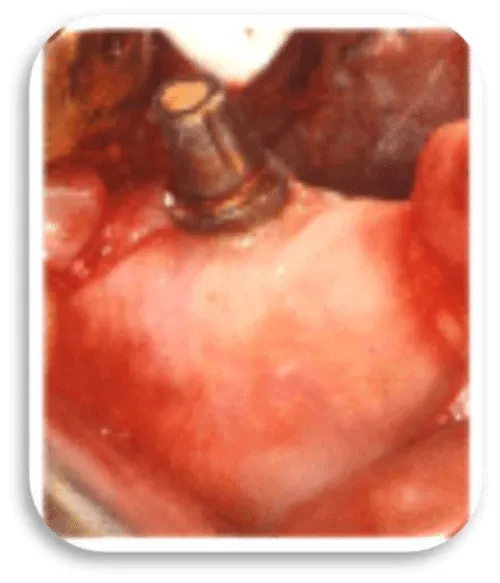

The first patient was at the age of 48 with male gender and generally with good health. There are no contraindications to make oral surgery. The patient is not allergic to any medication. A dental implant was placed 12 months ago (Figures 11,12), the dental implant’s position was 46. The implant was 4.1 mm in diameter and 12 mm in length. The patient has peri-implantitis, a RTG intraoral radiography image was recorded and marginal bone resorption was observed. The depth of the gingival sulcus was 10mm. Dehiscencia was seen in the patient from the buccal side of the implant (Figure 13). The bone defect was closed with a bone graft (Figures 14-16).

Before placing the dental implants, it is necessary to take an exhaustive history of the patient, to make the diagnosis and the plan of therapy. The procedure for implanting a dental implant involves first giving a local anesthetic a scalpel of size 15 and taking a sulcus incision, the buccal length of the implant site, and a vertical relaxation incision to protect the adjacent papilla. Before the initial osteotomy, we approach which measurement of the diameter of the alveolus and we estimate its architecture using special depth lines. Initial osteotomy is performed with the help of special borers. When doing osteotomy, we should pay attention to the depth due to the restorative platform that should not be deeper than 2-3mm apical from the cement enamel boundary of the future final restoration. Placement of the implant is carried out with a torsion force of 30Ncm. The first suture is set for the correct positioning of the cortical margin of the lamp using a thread for sutures of 5-0 or lower. After 7-10 days the strings are removed. After the completed modeling and soft tissue formation around the implant, the definitive restoration is made. Once the implant is placed in the bone, after a certain period the phase of their association, i.e. osteointegration and fibrous integration, is followed. After the osteointegration of the implants, the opening of the buried implants, mounting of the abutment and preparation of a prosthetic superstructure is followed. After the selection of the suprastructure, we approach the fingerprint for the working model, the prosthetic compensation is made and the definitive setting of the suprastructure and the prostitution fee follows [1].